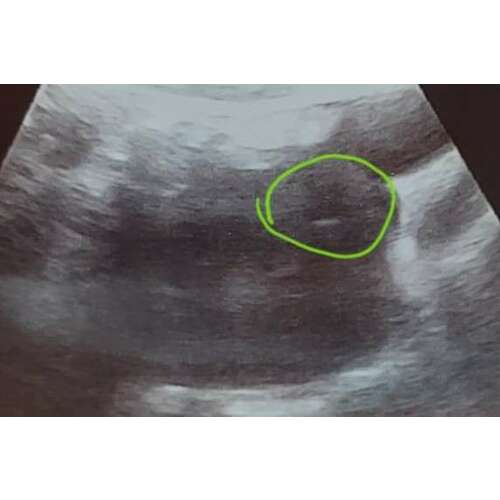

hey! dat witte op je foto is niet het embryo maar de luchtbel die ontstaat bij het inbrengen van het embryo, dat is nu nog zo klein, dat kun je nog niet zien op een echofoto :)

Haha jaa ze zeiden t tegen mij dat ie daar zat, vandaar :)